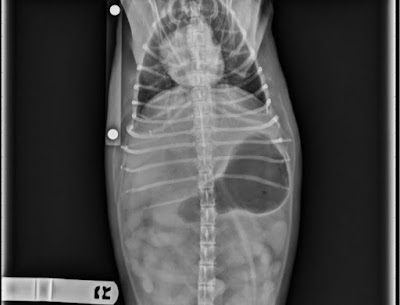

Unfortunately, many times pets, either by choice or by accident, present with over distended stomachs. Sometimes it is by getting into extra food or the trash cans. In other cases there is no obvious cause of the swelling. In the case below, a young puppy overate, then vomited, and aspirated food into his lungs. WHAT IS CLASSICAL BLOAT/DILATION? HOW IS THIS DIFFERENT FROM VOLVULUS?Bloat, a veterinary emergency in dogs, is a condition in which the stomach is distended with air, more scientifically called Gastric dilation. When the dilated stomach rotates 90 to 360 degrees it called gastric dilation and volvulus (GDV).

WHAT ARE THE SIGNS NOTED BY OWNERS?They are often that of acute distress: distended abdomen, pain, drooling, retching, increased heart rate, and difficulty breathing.EXPLAIN THE SEQUENCE OF EVENTS LEADING TO THE RAPID CRISIS?Due to a compromise of the circulatory system from a compression of vessels by the dilated stomach, acute collapse, shock, and even death may come quickly. The severe shock comes quickly and is accompanied by death of the stomach lining, enlarged spleen, and even stomach rupturing which releases toxins into the abdomen and general circulation. Death may happen in as little as 4 to 6 hours, and it the second leading cause of death in large breeds of dogs, second only to cancer.ARE THERE COMMON FINDINGS ON RADIOGRAPHS (X-RAYS)?Radiographs demonstrate a severely enlarged, gas-filled stomach that if twisted has several compartments called a “double bubble” that may ping when thumped.